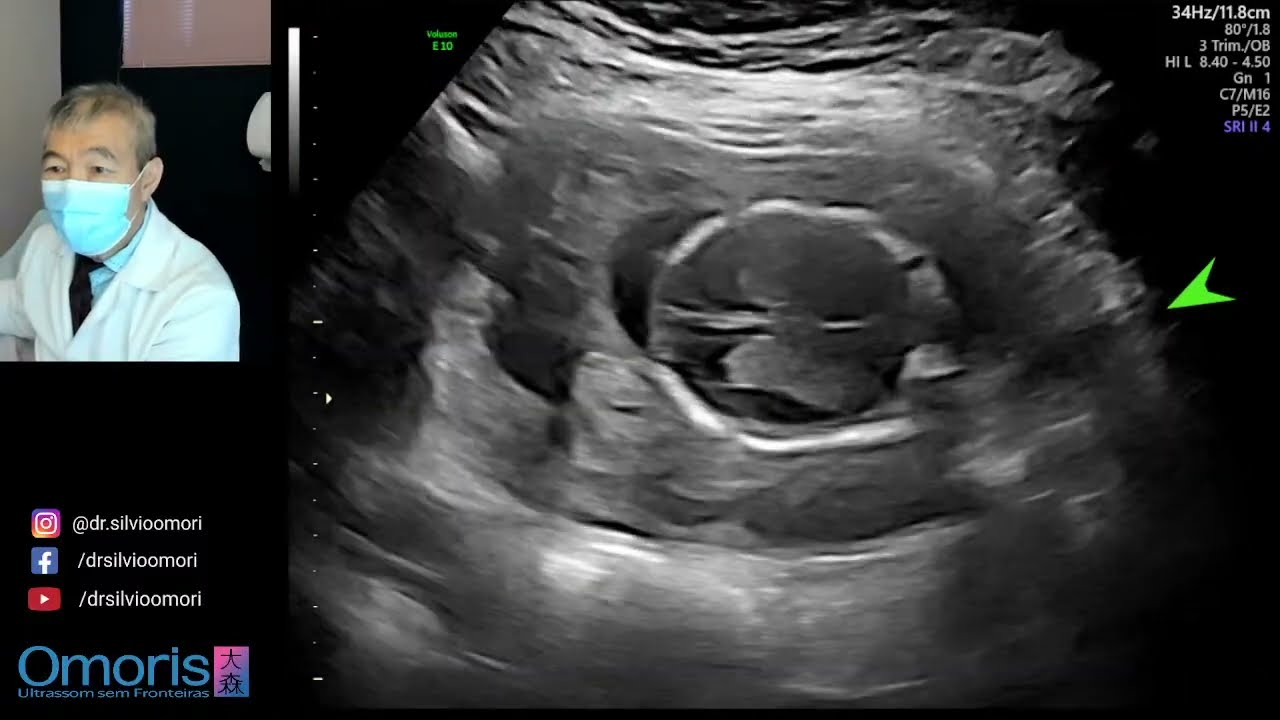

16 Semanas da gestação!!

Olá Liorálovers, entre no nosso grupo: https://bityli.com/PbZwb7P Se você é nova aqui, inscreva-se no canal: ‪@laurapadilhaparteira‬ Grandes coisas estão acontecendo. Seu bebê está crescendo rapidamente e prestes a passar por outro surto de crescimento massivo. Provavelmente, você engordou nas últimas semanas (2 a 4kg), mas isso é apenas um guia, pois cada gravidez é diferente. O sistema nervoso continua a se desenvolver e isso permite que o bebê comece a mover os braços e as pernas. Você poderá sentir seu bebê chutando a partir da próxima semana , o que é algo emocionante de se esperar. Esta é uma boa semana para planejar e fazer as coisas. Faça uma lista de coisas a fazer e comece a marcar as coisas - é incrivelmente terapêutico. Coloque 'meu tempo' na lista, caso você esqueça que também é importante. Você pode acessar as semanas anteriores nesse link:    • 4 semanas de gravidez!   Saiba mais sobre minha comunidade aqui 👇💕: http://parirfeliz.com.br/COMUNIDADE_P... É de Cuiabá, MT? Conheça nosso atendimento aqui 👇💙: https://www.liora.com.br/ "Parto não tem replay. É muito mais que, simplesmente dar à luz a um bebê. É uma experiência transformadora que nos marca para o resto da vida."